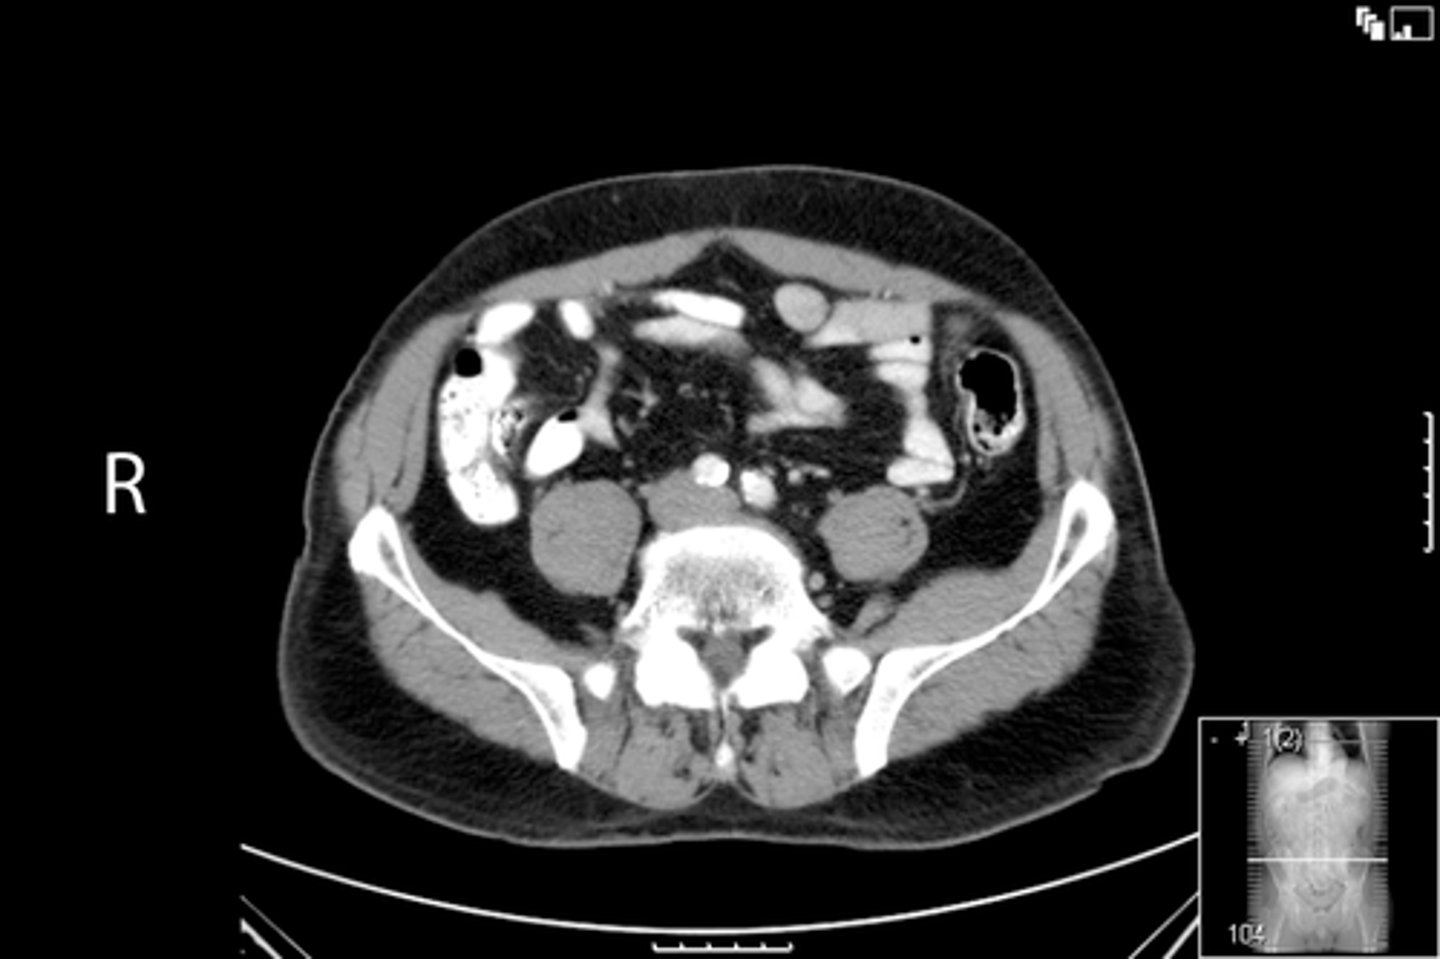

Axial bony pelvis CT

What is the image?

38

L acetabulum

What is indicated in the image?

<p>What is indicated in the image?</p>

39

New cards

L femoral head

40

L piriformis muscle

41

R femoral head

42

R piriformis muscle

43

R acetabulum (posterior part)

44

Sacrum